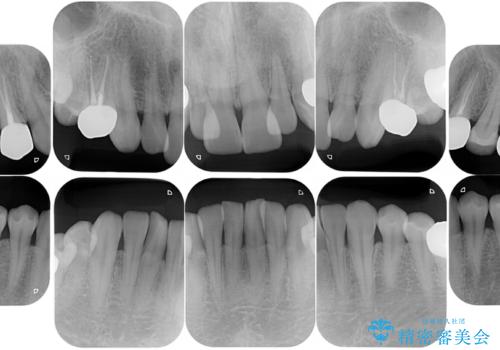

- お口の中にある銀歯を無くしたいとご相談にいらした方です。

適合の良いセラミックにてやり替えを行いました。

元々噛む力が強く、日常的に歯ぎしりもされるとの事でしたので、歯が割れてしまうリスクを軽減させるため、歯全体を覆うクラウンをメインに補綴治療を行いました。

適合不良の補綴物は二次的な虫歯発生のリスクが高まります。

自費診療で用いられる材料は保険適応の材料に比べて、より精密で適合の良い被せ物作ることができるため、長期的な虫歯のリスクを大幅に減らすことが可能です。